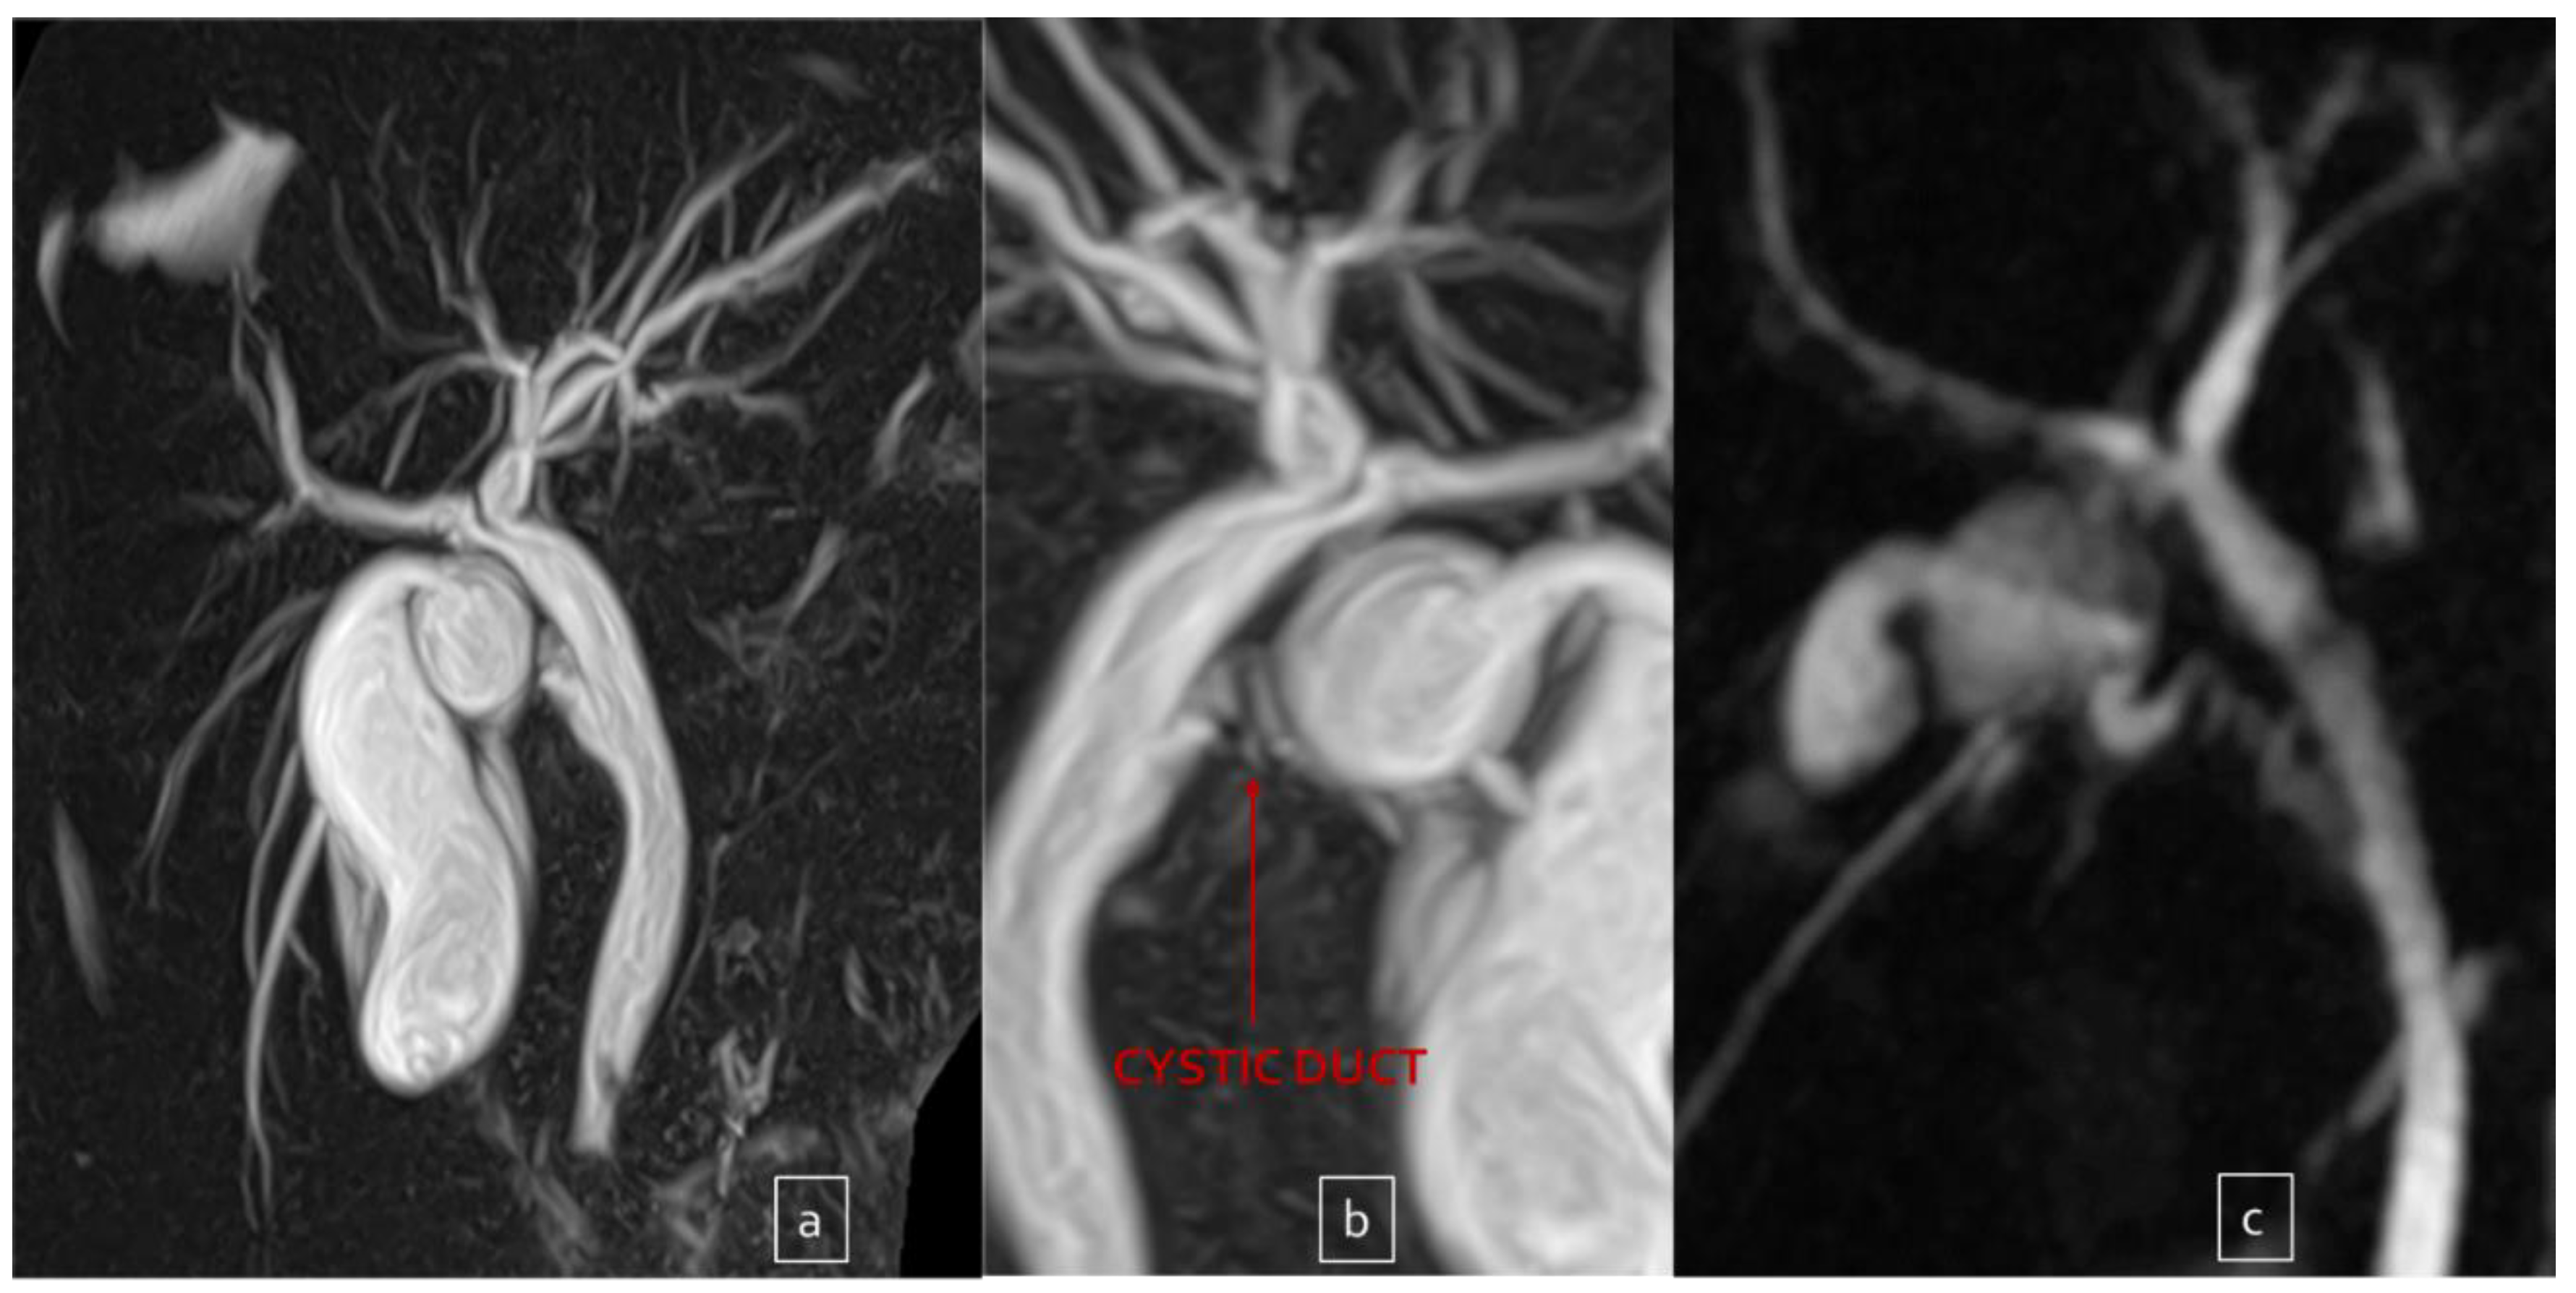

Out of these five difficult cases, laparoscopic cholecystectomy was totally completed in three cases (66.7%) and a subtotal cholecystectomy was performed in the other two (33.3%). There was no conversion to open surgery. Surgical difficulty was due to dysmorphic inflamed gallbladder with a dilated infundibulum and a tiny, convolute cystic duct (Figure 1a–c) in one case (20%); dense adhesions at the triangle of Calot due to the chronic inflammation in another case (20%) (Figure 2); an anomaly in the biliary tract anatomy in which the cystic duct projected into an aberrant right anterior hepatic duct and together they flowed into the common bile duct (20%) (Figure 3); and difficult trocar placement and reduced camera work due to the scoliotic attitude of two patients affected by Rett Syndrome (40%) (Table 2). None of these complex cases had Mirizzi syndrome or cholecystoenteric fistulas.

Figure 1.

Dysmorphic and dilated infundibulum ((a,b) front and back view) in a patient with recurrent cholecystitis. And results after partial cholecystectomy (c).